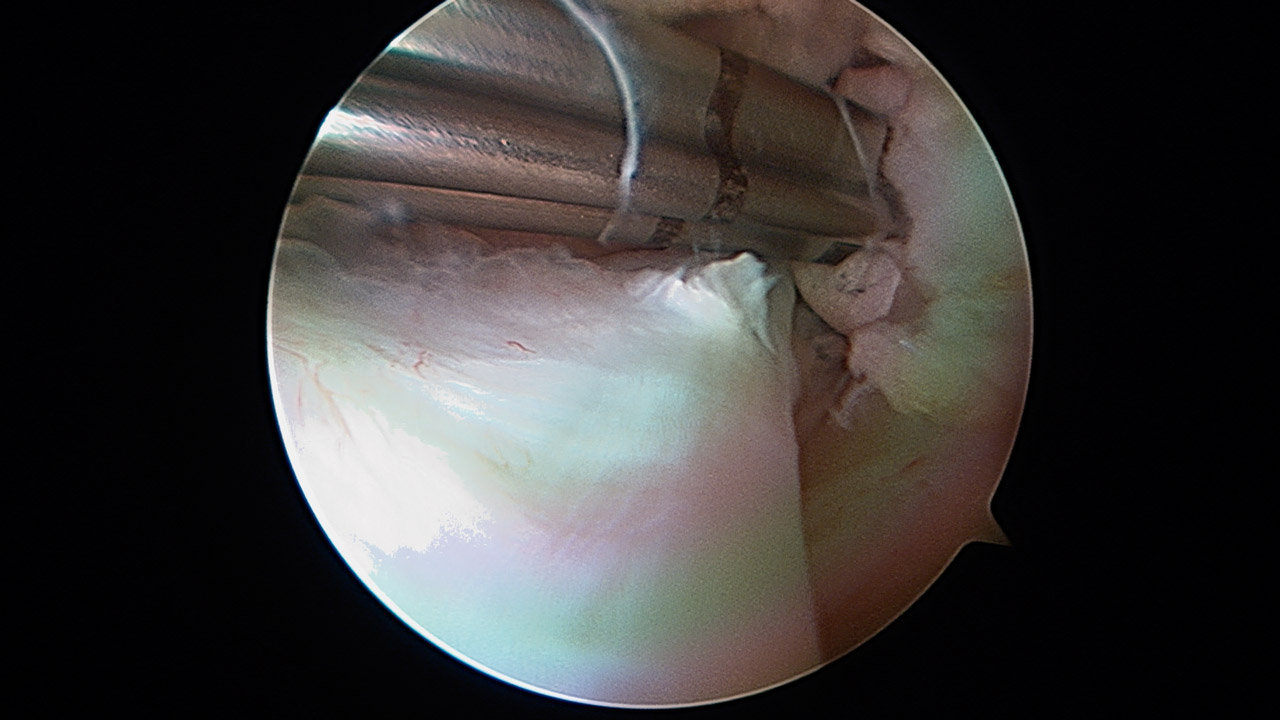

Ligamentoplastia anterior de hombro. Técnica quirúrgica

Anterior shoulder ligamentoplasty. Surgical technique